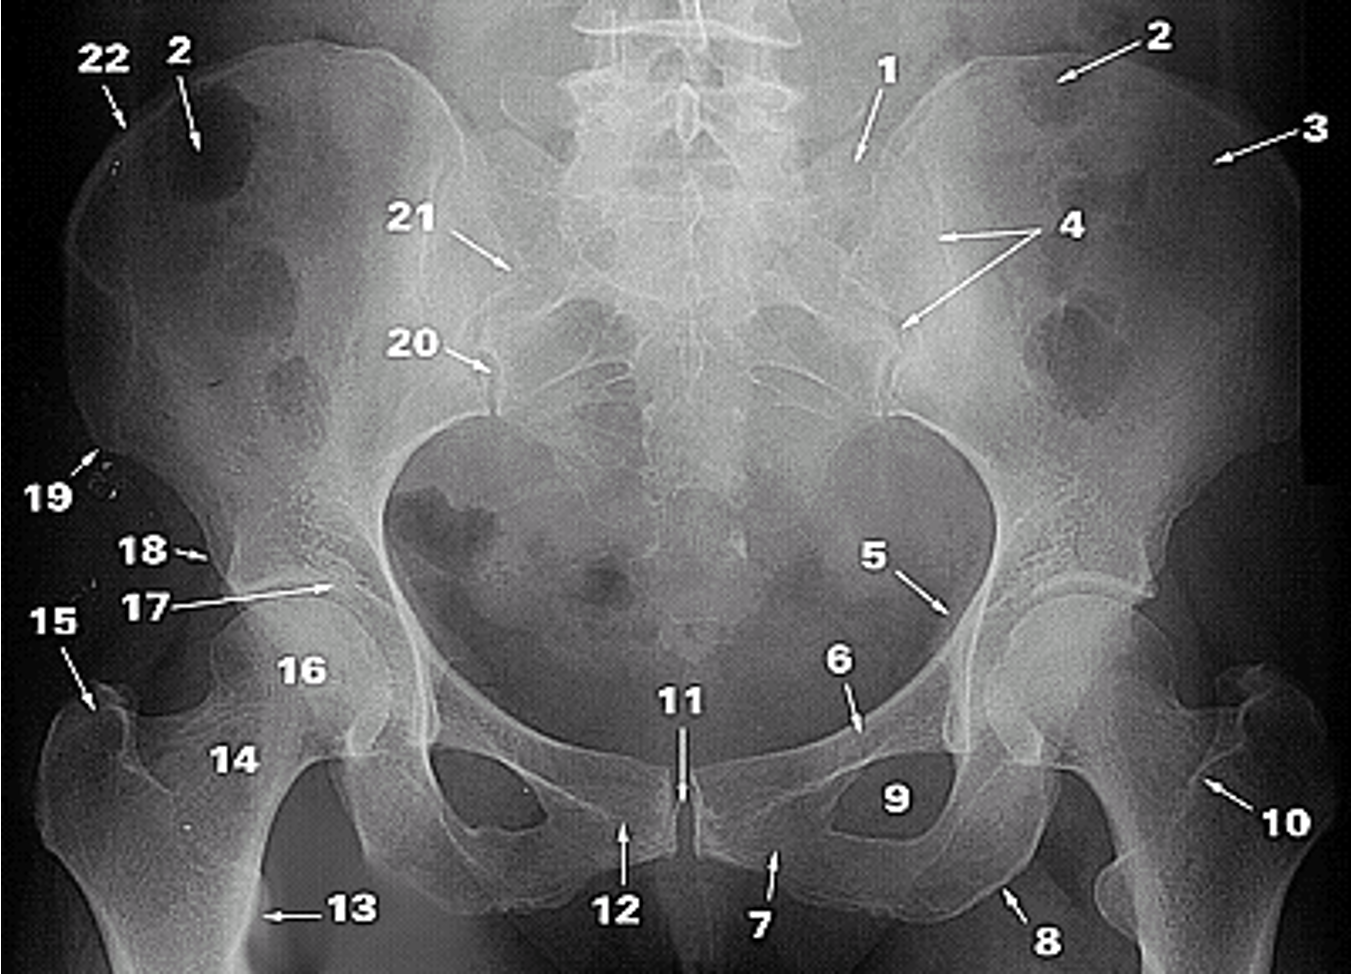

<p>1.</p>

1.

Lateral Part of the Sacrum

New cards

<p>2.</p>

2.

Gas in colon

<p>3.</p>

3.

Ilium

<p>4.</p>

4.

Sacroiliac Joint

<p>5.</p>

5.

Ischial Spine

<p>6.</p>

6.

Superior Ramus of Pubis

<p>7.</p>

7.

Inferior Ramus of Pubis

<p>8.</p>

8.

Ischial Tuberosity

<p>9.</p>

9.

Obturator Foramen

<p>10.</p>

10.

Intertrochanteric Crest

<p>11.</p>

11.

Pubic Symphysis

<p>12.</p>

12.

Pubic Tubercle

<p>13.</p>

13.

Lesser Trochanter

<p>14.</p>

14.

Neck of Femur

<p>15.</p>

15.

Greater Trochanter

<p>16.</p>

16.

Head of Femur

<p>17.</p>

17.

Acetabular Fossa

<p>18.</p>

18.

Anterior Inferior Iliac Spine

<p>19.</p>

19.

Anterior Superior Iliac Spine

<p>20.</p>

20.

Posterior Inferior Iliac Spine

<p>21.</p>

21.

Posterior Superior Iliac Spine

<p>22.</p>

22.

Iliac Crest